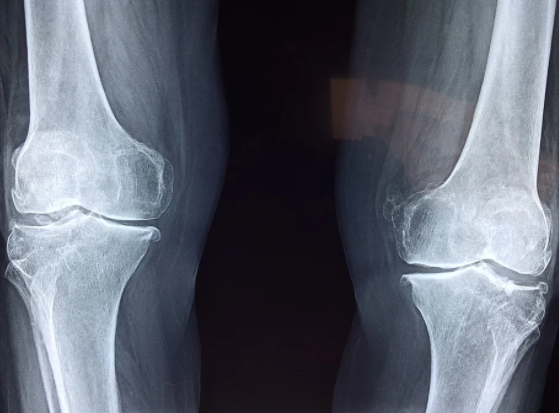

우리 몸에서 가장 많은 움직임이 있는 곳 중 하나가 바로 무릎일 것이다. 그만큼 무릎에 통증이 생긴다는 것은 곧 움직임에 제한이 생긴다는 것이고 연골에 그만큼 손상이 있다는 것이라고 짐작해볼 수 있다.

무릎 연골이라는 것은 한번 손상되기 시작하면 자연적으로 치유되지 않고, 계속 방치하게 되면 손상 부위가 점점 커지게 되어서 퇴행성 관절염을 앞당기게 되는 원인이 된다.

무릎 관절에 어떤 이유가 되었든 부담을 주게 되면 연골을 손상시켜서 무릎 관절염을 발생시키기도 한다.

무릎 연골 관절에는 허벅지뼈와 정강이뼈가 맞닿아있다고 한다. 이들의 뼈 끝에 있는 골연골은 뼈가 서로 부딪히면서 손상이 되지 않도록 하는 역할을 하게 되는데, 우리가 무릎에 무리를 줄 수 있는 행동이나 운동을 반복하게되면 뼈를 감싸고 있는 연골이 손상되기 때문에 평소에 무릎이 자주 아프다면 아래에서 언급하는 무릎 연골 손상 대표적 증상 TOP 6에 대해서 알아보고 자신이 해당하는지 파악해보기 바란다.